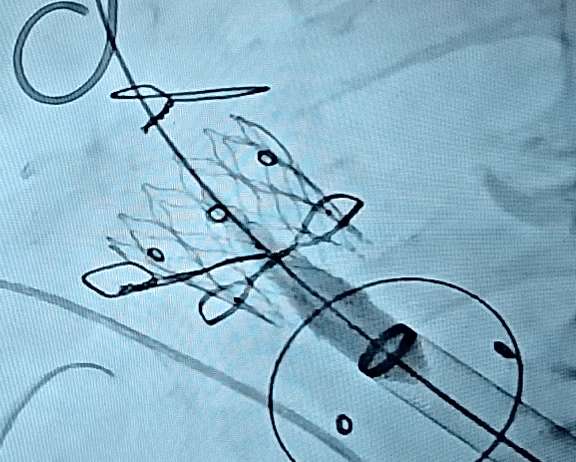

康复大学青岛中心医院林明山教授分享一例“双瓣一站式”高难度VIV病例,深刻展现自膨短瓣在生物瓣衰败VIV中的应用价值。患者83岁男性,于2010年行主动脉瓣置换术、二尖瓣置换术及三尖瓣成形术,现主动脉瓣和二尖瓣生物瓣均出现重度反流,术前超声/CT充分评估后,决定采用经心尖入路,先行主动脉瓣瓣中瓣植入术(TAVR-VIV),顺利送入ScienCrown TAVTA 23mm瓣膜,得益于该款瓣膜短瓣架设计,完全释放后对血流影响小,因此TAVR-VIV术中无需起搏,瓣膜初次释放位置稍浅,部分回收调整瓣膜深度重新释放,即刻造影示瓣膜位置良好,无张力脱钩瓣膜位置稳定,术后TEE示主动脉瓣平均跨瓣压差仅4mmHg。随后行二尖瓣瓣中瓣植入术(TMVR-VIV),经心尖入路植入ScienCrown TAVTF 29mm瓣膜,主动脉根部造影,冠脉显影良好无瓣周漏,术后TEE示二尖瓣平均跨瓣压差仅1mmHg。

TAVR-VIV术后造影

双瓣VIV术后最终造影